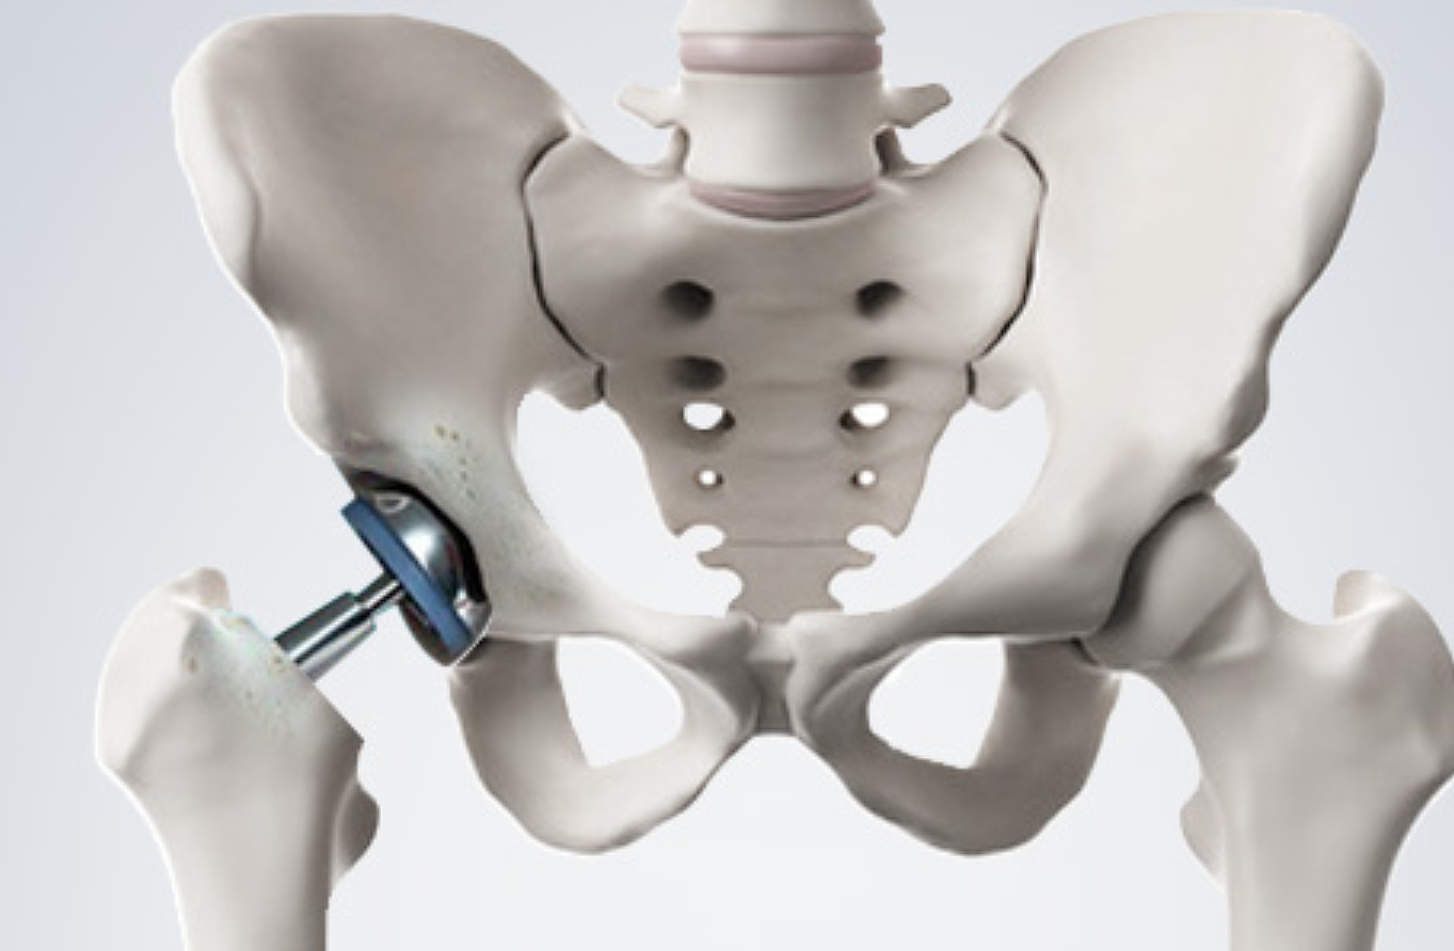

고관절 통증 증상은 조기에 발견하고 치료받는 것이 무엇보다 중요합니다. 고관절 손상이 심하지 않고 통증이 가볍다면 약물치료와 운동치료 등 보존적 치료를 통해 회복할 수 있습니다. 하지만 고관절 손상이 심하고 일상생활에 지장을 줄 만큼의 심한 고관절 통증 증상이 있는 경우라면 괴사된 관절을 제거하고 인공관절을 삽입하는 고관절의 인공관절 치환술을 해야 합니다.